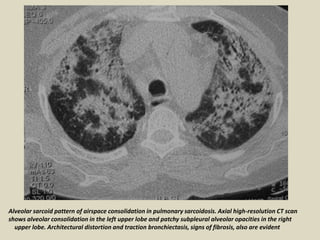

Alveolar sarcoid pattern of airspace consolidation in pulmonary sarcoidosis. Axial high-resolution CT scan

shows alveolar consolidation in the left upper lobe and patchy subpleural alveolar opacities in the right

upper lobe. Architectural distortion and traction bronchiectasis, signs of fibrosis, also are evident